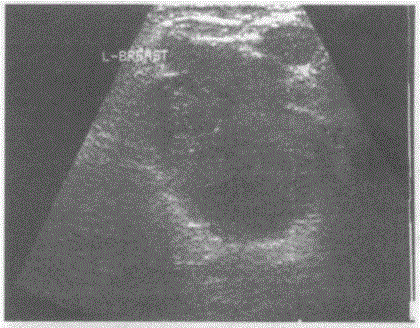

问题 临床资料:女,42岁,查体时发现左乳腺一肿物,活动度差,质硬。 超声综合描述:左乳外上象限可见4.1cm×3.0cm低回声区,形态不规则,边界不整,无包膜,内回声不均。 超声提示:

选项 A.乳腺癌 B.乳腺炎 C.乳腺脓肿 D.乳腺纤维腺瘤

答案 A